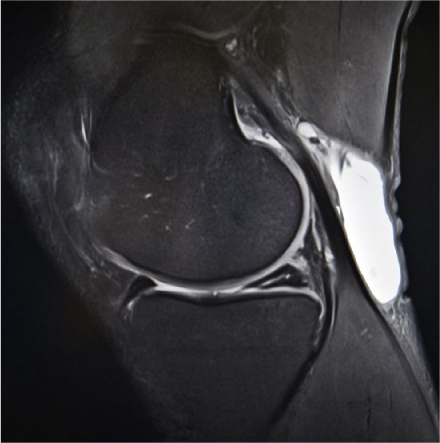

Geen MRI-scan aanvragen voor jonge patiënten met traumatische knieklachten is in deze tijd een uitdaging.

© iStock